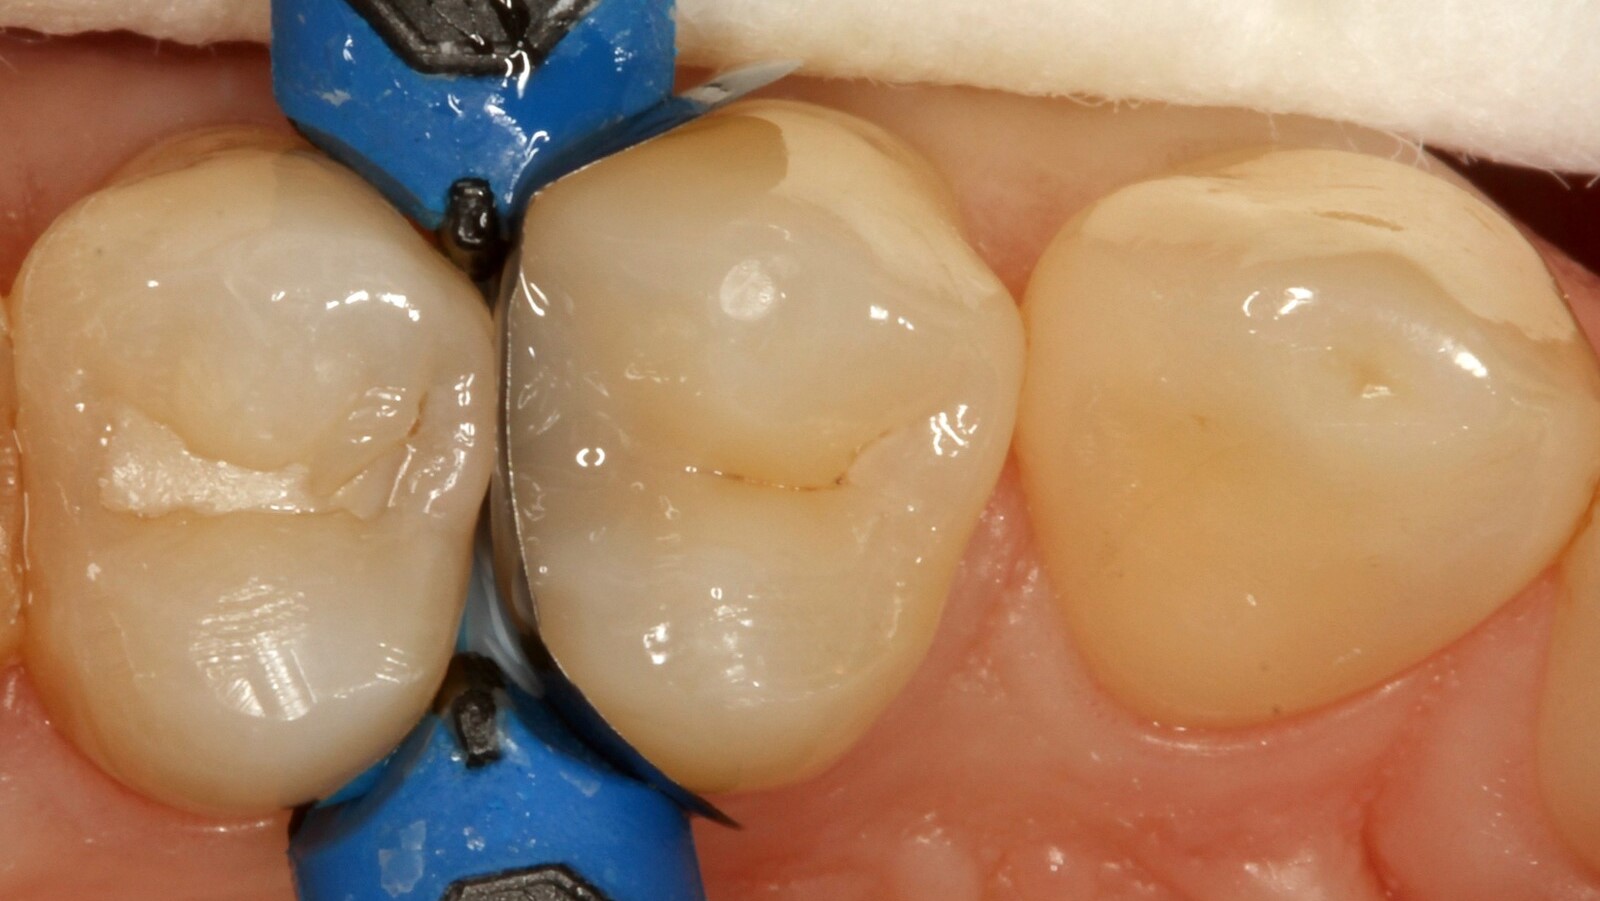

Professor Ernst identifizierte zunächst die versteckte Karies und öffnete die kariöse Läsion, um dem Patienten das Problem zu veranschaulichen (Abb. 1-2). Anschließend exkavierte er die Karies, präparierte die Kavität und setzte eine Teilmatrize ein (Abb. 3), bevor er die Kavität mit Adhäsiv versiegelte (Abb. 4). In einem einzigen Schritt füllte er die Kavität mit Venus Bulk Flow ONE (Abb. 5). Nach der Fertigstellung polierte Prof. Ernst die Restauration (Abb. 6) und fertigte ein Kontrollröntgenbild an, das ebenfalls die hervorragende Röntgenopazität von Venus Bulk Flow ONE zeigt (Abb. 7).

Einer der Hauptvorteile von Venus Bulk Flow ONE ist die zeitsparende Anwendung in einem Schritt, die gleichbleibende Ergebnisse garantiert. Das Komposit muss nicht geschichtet werden und kann daher in einem einzigen Schritt aufgetragen werden. Venus Bulk Flow ONE kann in Inkrementen von bis zu 4 mm mit der Bulk Filling- oder Bulk & Body-Technik verwendet werden. Das Komposit lässt sich aufgrund seiner guten Fließfähigkeit leicht platzieren. Nach dem Einbringen in die Kavität wird das Komposit mit einem Lichthärtegerät ausgehärtet, um den Restaurationsprozess abzuschließen.